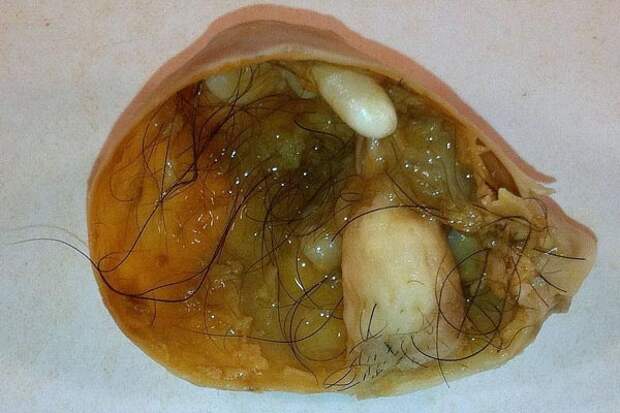

Дермоидная киста — киста, внутри которой содержатся волосы, волосяные фолликулы и сальные железы. Иногда в ней могут находиться также зубы, глаза и другие части тела